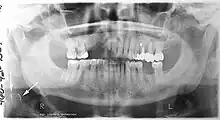

Epidemiology: general public and high risk groups

Additional research projects have further determined the prevalence rate of these atheromas in the general population (3–5%)[8][9] and among high-risk groups (over 25% in: recent stroke victims,[10] individuals with obstructive sleep apnea syndrome,[11][12][13] postmenopausal women,[14] type 2 diabetics,[15][13][16] individuals with dilated cardiomyopathy,[17][13] and among individuals who have received radiotherapy directed at the neck,[18][19]). These findings have been corroborated by other several other researchers.[20][21][22][23][13]

Atherosclerosis is attributed to risk factors that include cigarette smoking, hyperlipidemia, obesity, diabetes mellitus, and hypertension (high blood pressure). These factors, however, do not fully account for the risk of disease. Atherosclerosis has been conceptualized as a chronic inflammatory response to endothelial cell injury[24] and dysfunction possibly arising from chronic dental infection. In 2010, using the previously validated Mattila panoramic radiographic index to quantify the totality of dental infection (i.e., periapical and furcal lesions, pericoronitis sites, carious tooth roots, teeth with pulpal caries, and vertical bony defects), Friedlander’s group determined that individuals with carotid artery atheromas on their panoramic radiographs had significantly greater amounts of dental infection/inflammation than atherogenic risk-matched controls devoid of radiographic atheromas.[25][26] While the Mattila index had been previously used to relate the extent of dental infection to coronary artery disease, this research is the first to link the full range of dental disease that it measures to panoramic radiographs evidencing calcified carotid artery atherosclerosis.